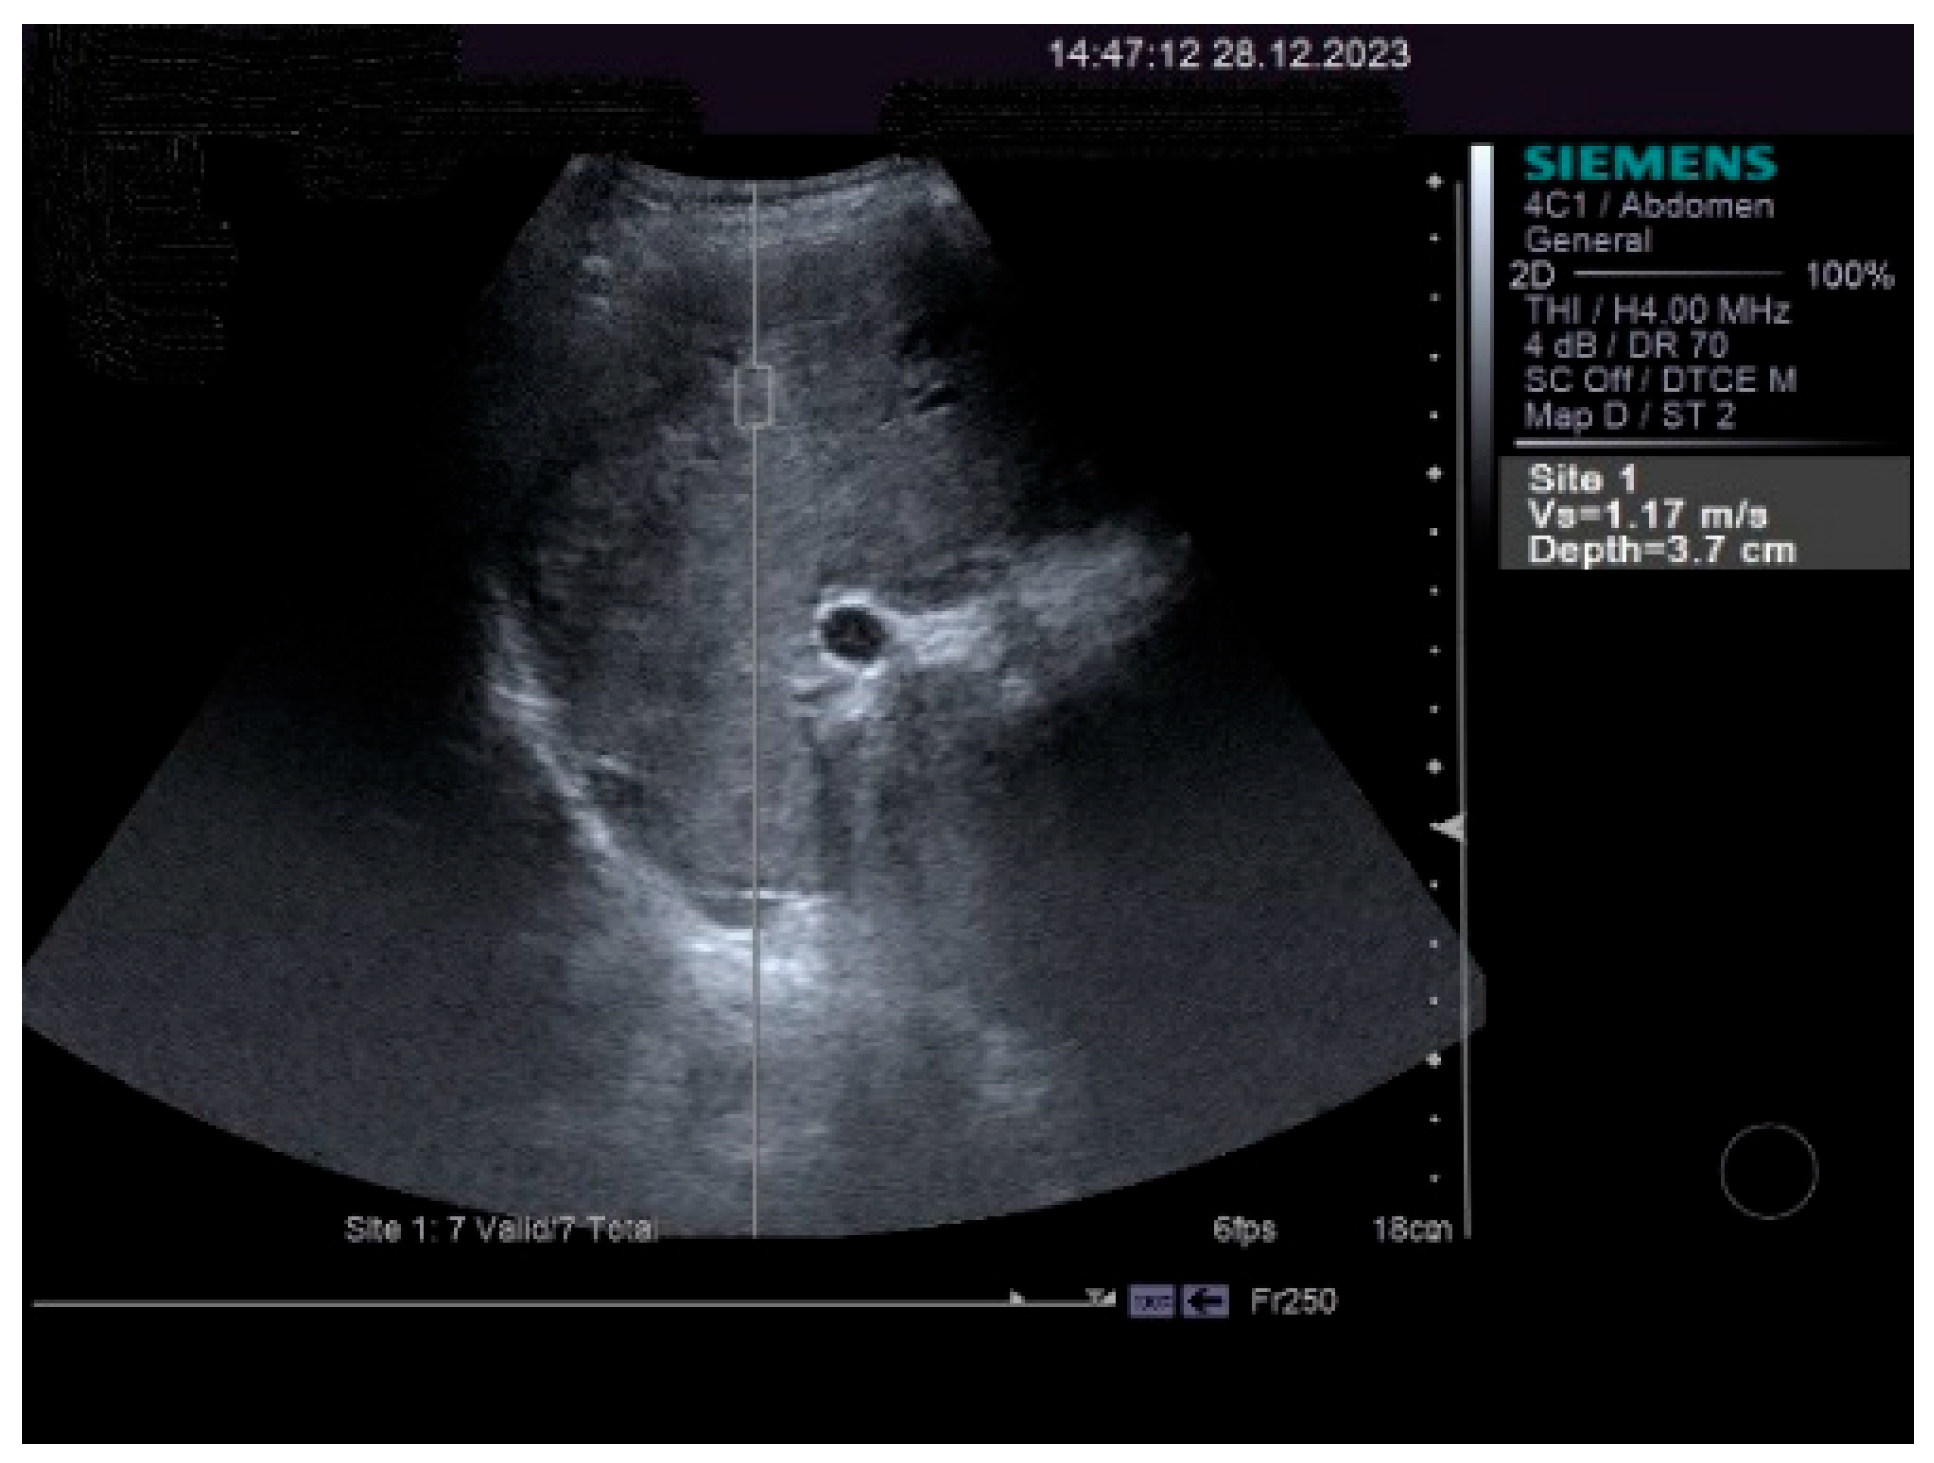

The measurements of the resistivity index of the hepatic artery at the liver hilum revealed increased values (HARI = 0.79). However, the liver elastography demonstrated a low stiffness. The measurements were made using the acoustic radiation force impulse (ARF)I method, by point shear wave (p SWE) elastography, and the obtained median value was 1.24 m/s, IQR = 0.12, equivalent to an F2 Metavir fibrosis score. Therefore, the diagnosis of liver cirrhosis was highly improbable. The elastography of the right liver lobe performed by the ARFI method, pSWE, is presented in Figure 5.

Figure 5. p SWE elastography of the right liver lobe.